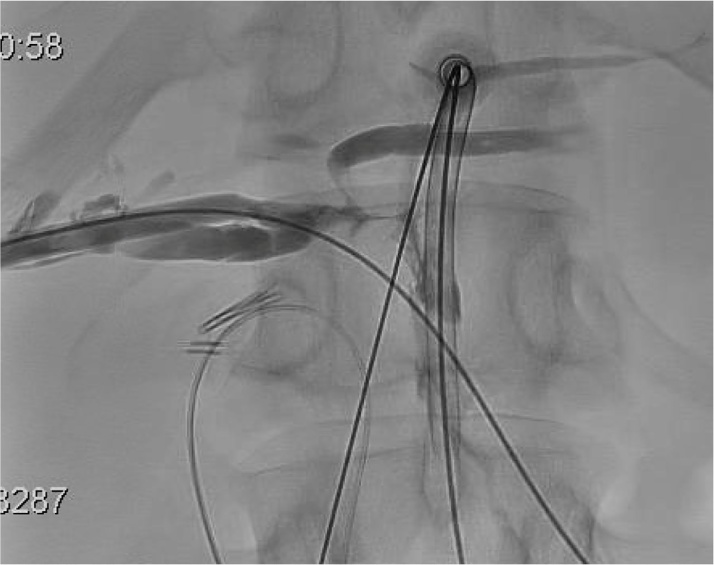

Fig. 6.

Both sheaths were identified passing through the common hepatic duct.